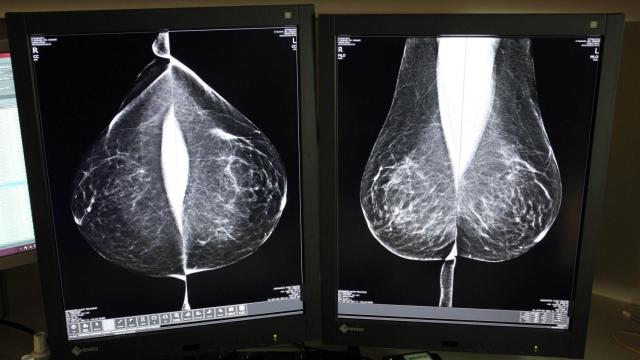

Cáncer de mama